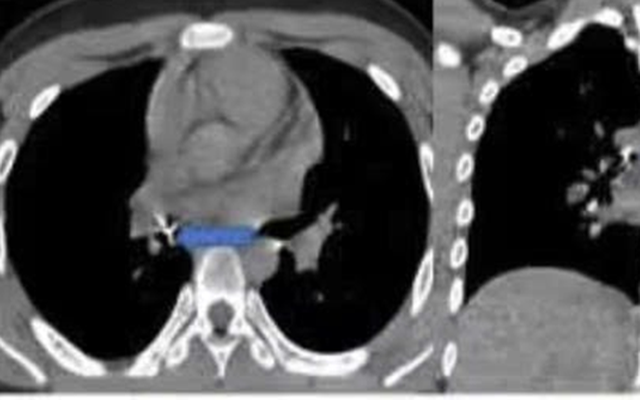

Hình ảnh nội soi ống mềm gắp dị vật đinh ghim xuyên thành phế quản trung gian. Ảnh: BVCC

Ê-kíp đã cẩn trọng dùng kìm nội soi chuyên dụng gỡ phần đầu ghim khỏi thành phế quản, sau đó từ từ gắp cả dị vật ra ngoài. Toàn bộ thủ thuật diễn ra trong khoảng 15 phút và thành công.

Sau thủ thuật, bệnh nhi giảm ho, đỡ khó thở, còn cảm giác tức ngực nhẹ. Do xuất hiện biến chứng tràn khí trung thất và tràn khí dưới da vùng cổ, bệnh nhi tiếp tục được theo dõi và điều trị nội khoa tại Bệnh viện Phổi Trung ương.